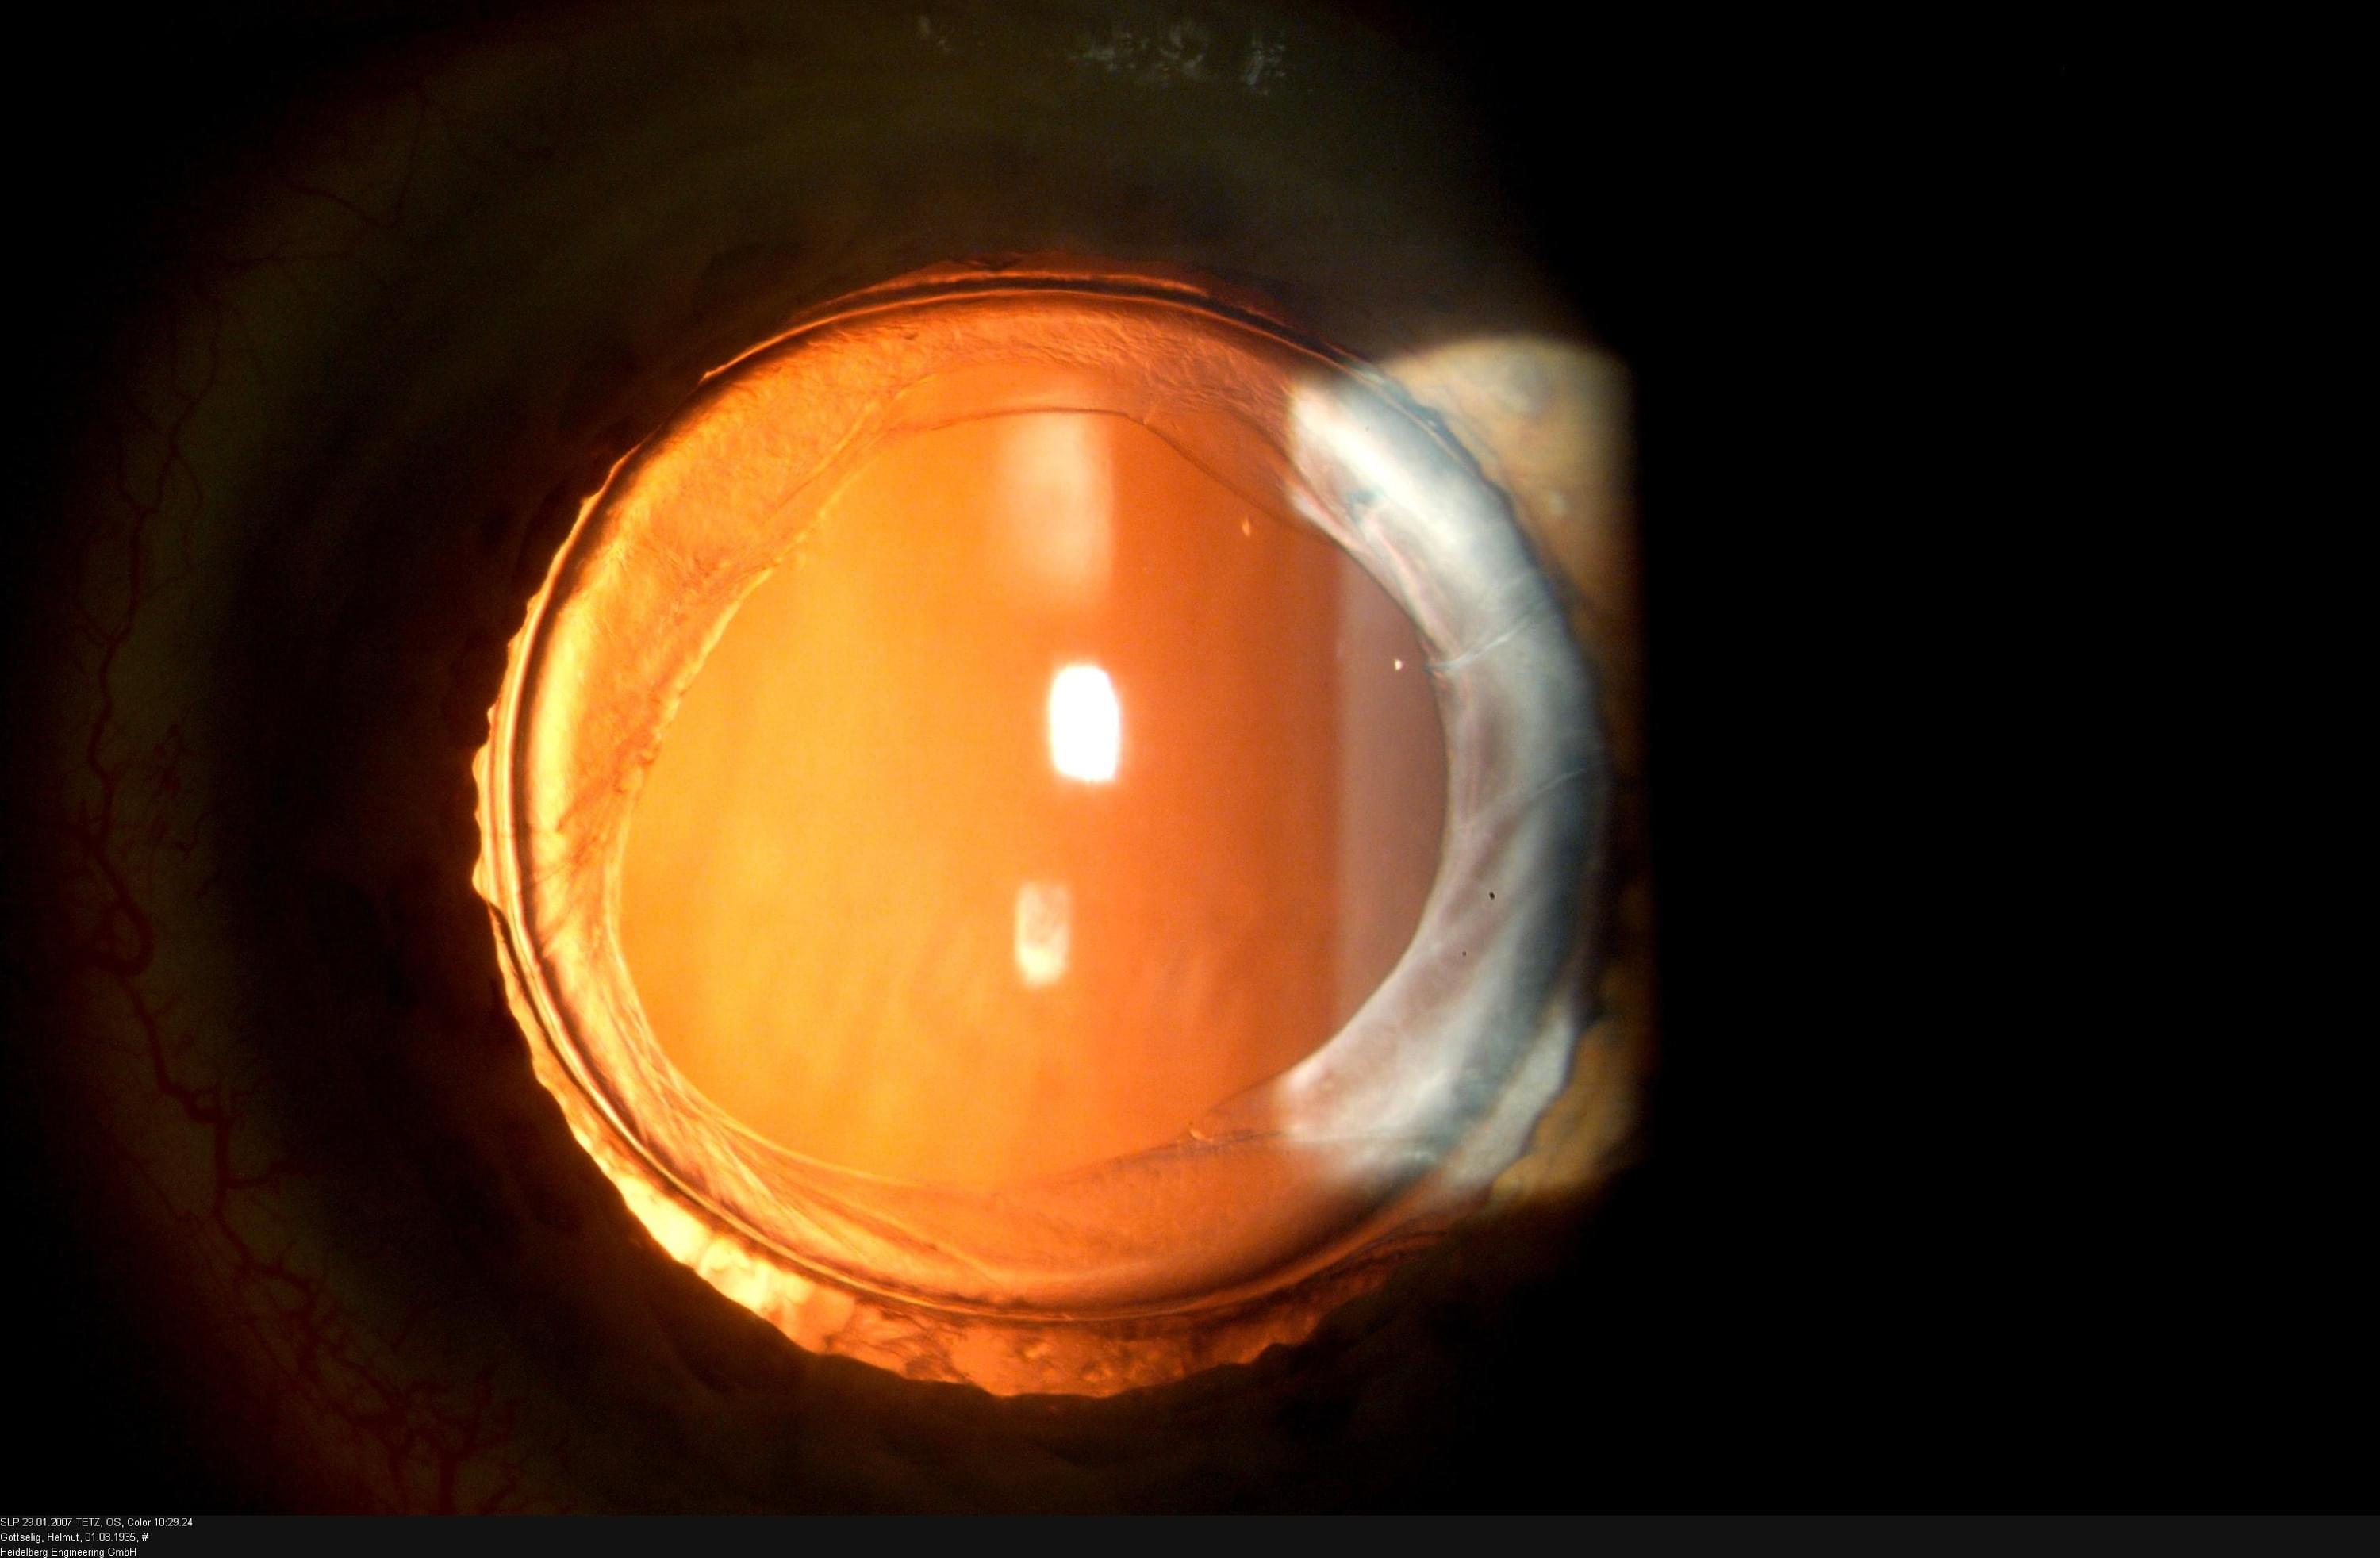

• modernste Messgeräte und Operationsmöglichkeiten

Rechtzeitige Premium-Diagnostik erlaubt uns rechtzeitige Interventionen

Viele Erkrankungen verlaufen unbemerkt über lange Zeit.

Daher muss mit technischen Mitteln eine umfassende Augenvermessung erfolgen, damit man frühzeitig reagieren kann.

Grauer Star - Makuladegeneration - Grüner Star

Mit uns an Ihrer Seite verlieren diese Erkrankungen ihren Schrecken.

Wir haben massgeschneiderte Lösungen für Ihre Probleme.